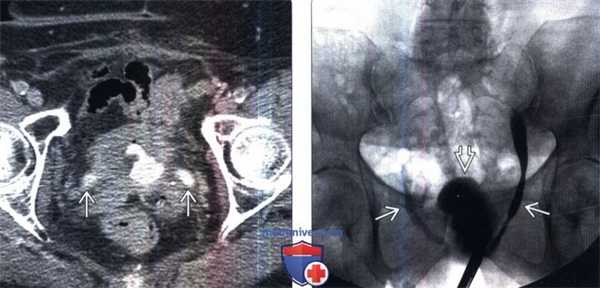

(Слева) КТ с контрастированием в отсроченную фазу, аксиальный срез: у пациента с анамнезом дистанционной лучевой терапии по поводу рака анального канала определяется заметное кольцевидное утолщение стенки мочевого пузыря с нарушением ее формы. Определяется прорастание инфильтрирующей опухоли в пузырно-мочеточниковое соустье, что вызвало двусторонний гидроуретеронефроз.

(Справа) Ретроградная цистография в передней проекции: у этого же пациента определяется нарушение контура и снижение растяжимости мочевого пузыря. Обратите внимание на двусторонний гидроуретер.